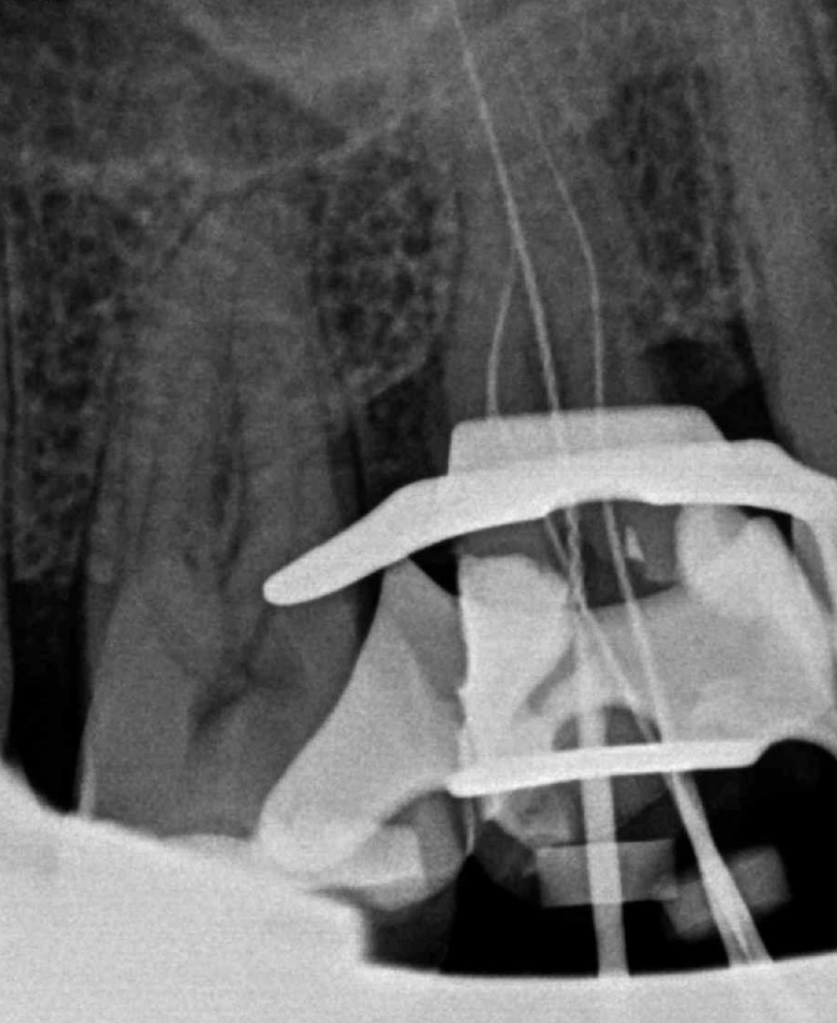

CALCIFICADOS

Premolar calcificado lesion